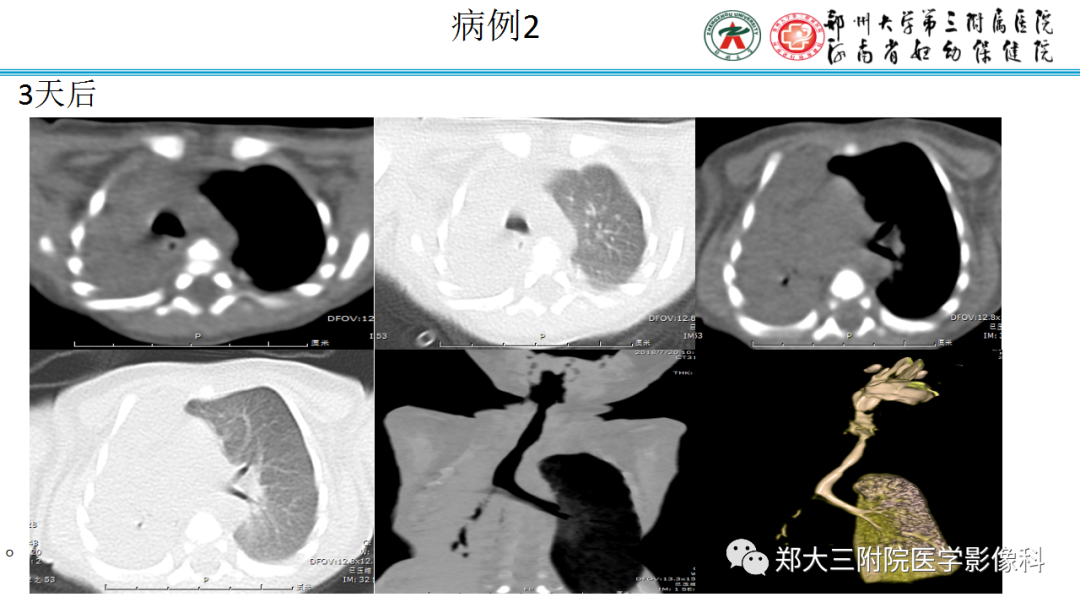

迅速增大的肺部结节,首先考虑良性,确诊需要肺穿  肺隔离症:易误诊为肺癌的占位性病变,肺穿刺禁忌!